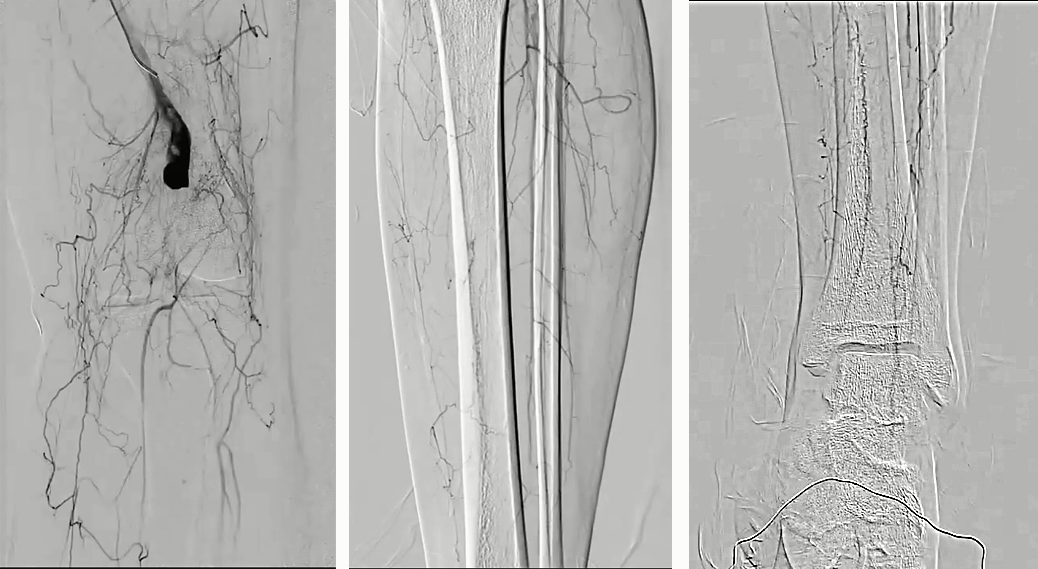

1. 右侧股动脉穿刺,翻山顺行造影显示腘动脉瘤及以远闭塞,仅胫前动脉及腓动脉的近中段显影,踝关节处小腿动脉显影不良,通过侧枝与踝下动脉沟通;

2. 由于顺行无法到达远端真腔,因此从腓动脉逆穿送入V-18导丝,经18支撑导管造影寻找真腔;

3. 在路图指引下支撑导管配合V-18导丝探查腘动脉真腔,V-18导丝经腘动脉跨过假性动脉瘤到达近端股浅动脉真腔,穿管成功,建立股浅动脉至腓动脉通道;

4. 用5F导管抽吸腘动脉闭塞段,未吸出血栓;

5. 路图下4mm×200mm球囊扩张自腘动脉远端至假性动脉瘤上端,4个大气压时患者诉疼痛。造影见腘动脉未显影;

6. 将导管向远端推送跨过动脉瘤,造影见腘动脉P1P2交界处血管破裂,远端仍未显影;将导管推送至P2段,见造影剂外溢和远端夹层形成;